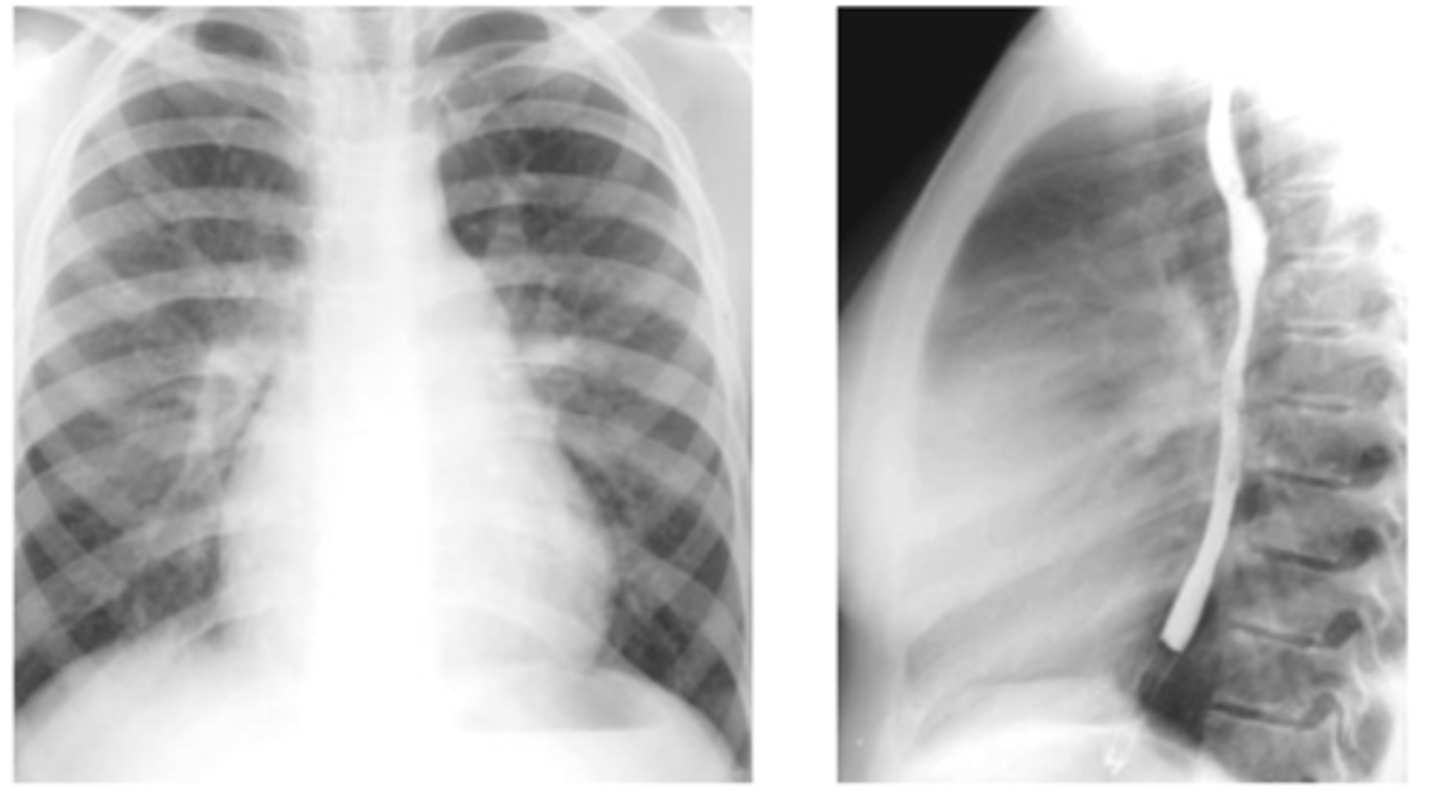

X-ray findings with atrial septal defect

-pulmonary artery

enlargement, right atrial and right ventricular enlargement.

-Film shows filling-in of retrosternal space and

increased size of the pulmonary artery.

<p>-pulmonary artery</p><p>enlargement, right atrial and right ventricular enlargement.</p><p>-Film shows filling-in of retrosternal space and</p><p>increased size of the pulmonary artery.</p>